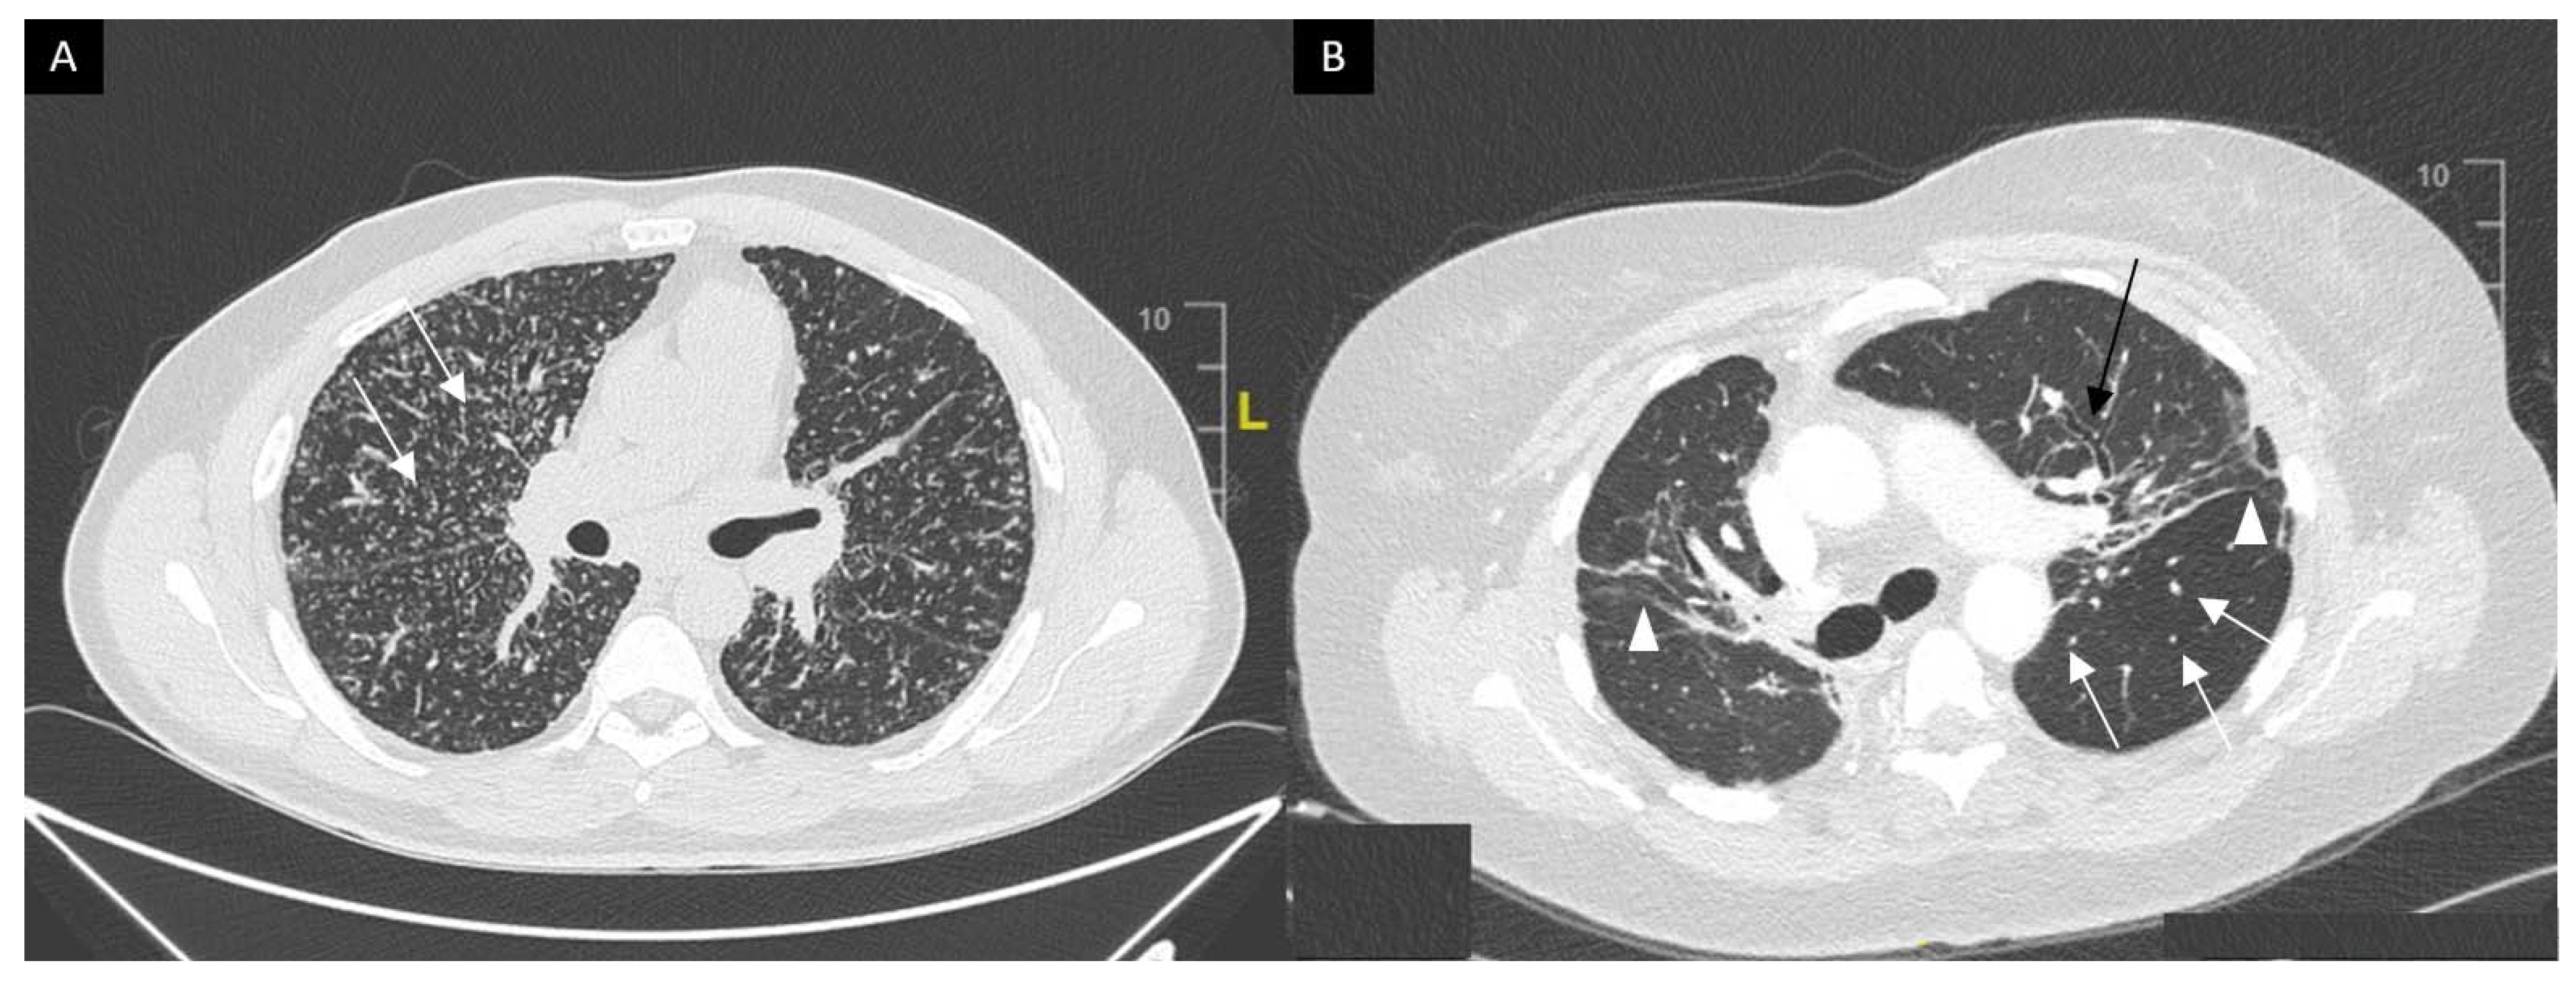

This system was developed prior to computed tomography (CT) and is widely used for its prognostic value. Mediastinal lymphadenopathy, especially right paratracheal and aorto-pulmonary locations, are commonly observed on chest CT. Calcifications [33] of lymph nodes may occur in sarcoidosis; they are usually chalky, focal and tend to be bilateral when present [33]. Chest CT is much more sensitive than CXR for the detection of lung nodules and subtle fibrosis. Pulmonary nodules tend to be tiny, usually termed “micronodules” ranging from 2 to 5 mm, typically located along the bronchovascular bundles, interlobular septa, interlobar fissures and subpleural regions, which constitute the “perilymphatic distribution (Figure 2A). Pulmonary fibrotic changes may be a dominant feature with typical features of architectural distortion, volume loss and bronchiectasis, which tend to predominate in the middle and upper lung zones (Figure 2B). Recently, the “dark lymph node” or the “cluster of black pearls” sign (defined by tiny round nodules each measuring 1–2 mm which are seen uniformly distributed throughout all or part of the lymph node) has been described as relatively specific of sarcoidosis with negative and positive predictive values of 96 and 91%, respectively [34]. The “galaxy” sign is also highly suggestive for sarcoidosis; it consists of a large nodule, usually with irregular boundaries, surrounded by a border of tiny satellite nodules. Alveolar, pseudo-alveolar consolidations, or diffuse ground glass are rarely the cause of sarcoidosis-associated radiological abnormalities [35].

Figure 2.

(A) Perilymphatic micronodules predominant in the right lung (white arrows). (B) Reticular opacities (white arrowheads), extensive traction bronchiectasis (black arrows) and perilymphatic nodules (white arrow) on lung windows. Findings consistent with sarcoidosis along with fibrosis.